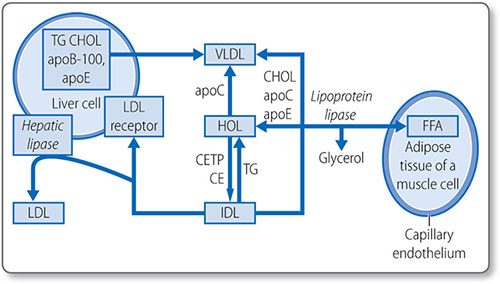

Figure 1.46: Biosynthesis of cholesterol. HMG-CoA, 3-hydroxy-3-methylglutaryl CoA. NADPH, nicotinamide adenine dinucleotide phosphate; ATP, adenosine triphosphate.

This process starts with the isomerization of isopentenyl pyrophosphate to form dimethylallyl pyrophosphate.

Formation of squalene epoxide The third stage is the cyclization of squalene to form squalene epoxide. This requires O2 and NADPH. Squalene epoxide then undergoes cyclization to lanosterol in a reaction catalyzed by cyclase. Lanosterol is then converted to cholesterol, a 27-carbon molecule, by the removal of three methyl groups and the reduction of a double bond by NADPH.

79Regulation of cholesterol synthesis Cholesterol synthesis is regulated by mechanisms that sense the cellular level of cholesterol and modify HMG CoA reductase levels and activity:

- Sterol regulatory element: a transcription factor that inhibits enzyme gene expression in the presence of sterols

- Non-sterol metabolites: derivatives of mevalonate inhibit enzyme gene expression

- AMP-activated protein kinase: phosphorylates and decreases enzyme activity when ATP levels are low

- Enzyme degradation is also tightly regulated.

Cholesterol absorption

Cholesterol esters in the gut are hydrolyzed by cholesterol esterases, secreted by the pancreas and small intestine, to free cholesterol. Cholesterol must be emulsified to be absorbed: conjugated bile acids form micelles with free cholesterol, fatty acids, monoglycerides, and phospholipids.

Most cholesterol is absorbed in the middle jejunum and terminal ileum through the transmembrane transporter protein Niemann–Pick C1-like 1 protein. 30–60% of dietary cholesterol is absorbed daily. Once absorbed into the intestinal mucosa cell, it is packaged into large lipoproteins called chylomicrons.

Cholesterol esterification

As free cholesterol is cytotoxic, it is esterified in the liver to cholesterol ester by acyl cholesterol acyl transferase. Cholesterol esters are stored in intracellular lipid drops and constitute 70% of plasma cholesterol.

Esterification requires energy-dependent activation of a fatty acid with CoA to form an acyl CoA. The acyl CoA reacts with a hydroxyl group on cholesterol to form an ester.

80Lipoprotein esterification Esterification also occurs in the blood, in lipoproteins, the lipid transport vesicles. This is catalyzed by lecithin-cholesterol acyl transferase and does not require CoA; instead a fatty acid is transferred from lecithin. The enzyme is activated by apolipoprotein A-I, the major apolipoprotein in high density lipoprotein (HDL). Cholesterol esters are in the hydrophobic core of the lipoprotein molecule (Table 1.21).

Lipid absorption and transport: lipoproteins

Lipoproteins are spherical particles with non-polar neutral lipids in their core (i.e. triglycerides and cholesterol esters) and more polar amphipathic lipids (i.e. phospholipids and cholesterol) on their surface (Figure 1.47). They also have apolipoproteins on their surface, which bind lipids, cell receptors and act as co-factors for enzymes of lipid metabolism (Table 1.22).

Types

Lipoproteins are classified by their physiochemical properties (Tables 1.21 and 1.23). Generally, larger lipoproteins contain more core lipids, triglycerides and cholesterol esters, and less protein.

Pathways

Lipoprotein metabolism has four main pathways with discrete functions in lipid transport.

|

- The exogenous pathway

- The endogenous pathway

- Intracellular cholesterol transport

- Reverse cholesterol transport.

The exogenous pathway

The exogenous lipoprotein pathway transports lipids absorbed by the intestine to the liver and peripheral cells (Figure 1.48).

- Chylomicrons are assembled in the endoplasmic reticulum of endocytes by combining triglycerides with apolipoprotein B-48

- They are secreted into the circulation, where they acquire additional lipoproteins (e.g. apolipoproteins E and CIIII) from HDL

- Apolipoprotein C-II activates lipoprotein lipase on the luminal surface of endothelial cells, which hydrolyzes chylomicrons to free fatty acids

- The free fatty acids are either taken up by adipose tissue and stored as triglycerides or taken up by muscle and used as an energy source.

|

Remnant particles Chylomicrons are progressively hydrolyzed to chylomicron remnant particles. The surplus phospholipids and apolipoprotein A-I, are transferred back to HDL. Remnant particles are taken up by the liver through via hepatic apolipoprotein E and B-48 receptors. The triglycerides returned to the liver are used to power the biosynthetic activity of the liver, or they are repackaged with apolipoprotein B100 and secreted as very-low-density lipoprotein (VLDL) particles.

The endogenous pathway

This pathway transfers triglycerides synthesized by/transferred to the liver to peripheral cells for energy metabolism (Figure 1.49).

|

Figure 1.48: The exogenous lipoprotein pathway. apo, apolipoproteins; CE, cholesteryl ester; CETP; cholesteryl ester transfer protein; CHOL; cholesterol; CM, chylomicrons; FFA, free fatty acids; HDL, high-density lipoprotein; IDL, intermediate-density lipoprotein; TG, triglycerides; VLDL, very-low-density lipoprotein.

Lipoproteins in the endogenous pathway contain apolipoprotein B-100, particularly VLDLs, which also contain apolipoprotein E and apolipoprotein C. The apolipoprotein C-II on the surface of VLDLs activates lipoprotein lipase on the surface of endothelial cells, which hydrolyze triglycerides to glycerol and fatty acids. The progressive hydrolysis of triglycerides in the core of a VLDL particle transforms it into intermediate density lipoprotein and eventually LDL.

About half of the apolipoprotein B100 particles in the exogenous pathway are removed by hepatic remnant receptors before undergoing complete hydrolysis. The remaining portion is converted to LDL. The triglyceride in LDL is further depleted by the cholesteryl-ester transfer protein, a plasma enzyme that removes triglycerides from LDL in exchange for cholesterol esters from HDL. During the transformation from VLDL to LDL, excess surface phospholipid and lipoproteins (except apolipoprotein B-100) are transferred to HDL.

Figure 1.49: The endogenous lipoprotein pathway. apo, apolipoproteins; CE, cholesteryl ester; CETP; cholesteryl ester transfer protein; CHOL; cholesterol; CM, chylomicrons; FFA, free fatty acids; HDL, highdensity lipoprotein; IDL, intermediate-density lipoprotein; LDL, low-density lipoprotein; TG, triglycerides; VLDL, very-low-density lipoprotein.